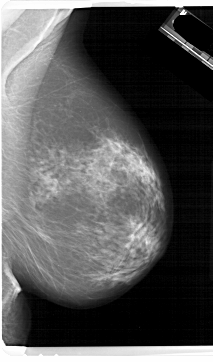

A_1657_1.LEFT_MLO

LEFT_MLO LINES 6721 PIXELS_PER_LINE 4246 BITS_PER_PIXEL 12 RESOLUTION 43.5 OVERLAY